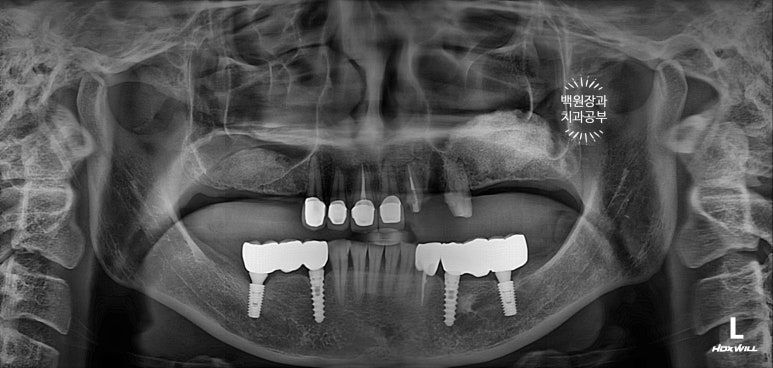

보시면 마치 없는 것처럼 보이지만, 앞니는 임시 브릿지로 해두었고...

왼쪽 위 임플란트부터 심어드렸습니다.

상악동 뼈이식 해놓은지 오래되어 뼈는 꽤나 단단한 상태였고, 큰 어려움 없이 임플란트를 심을 수 있었어요!

보시면 나란히 예쁘게 잘 심겨있는 임플란트를 보실 수 있을겁니다.